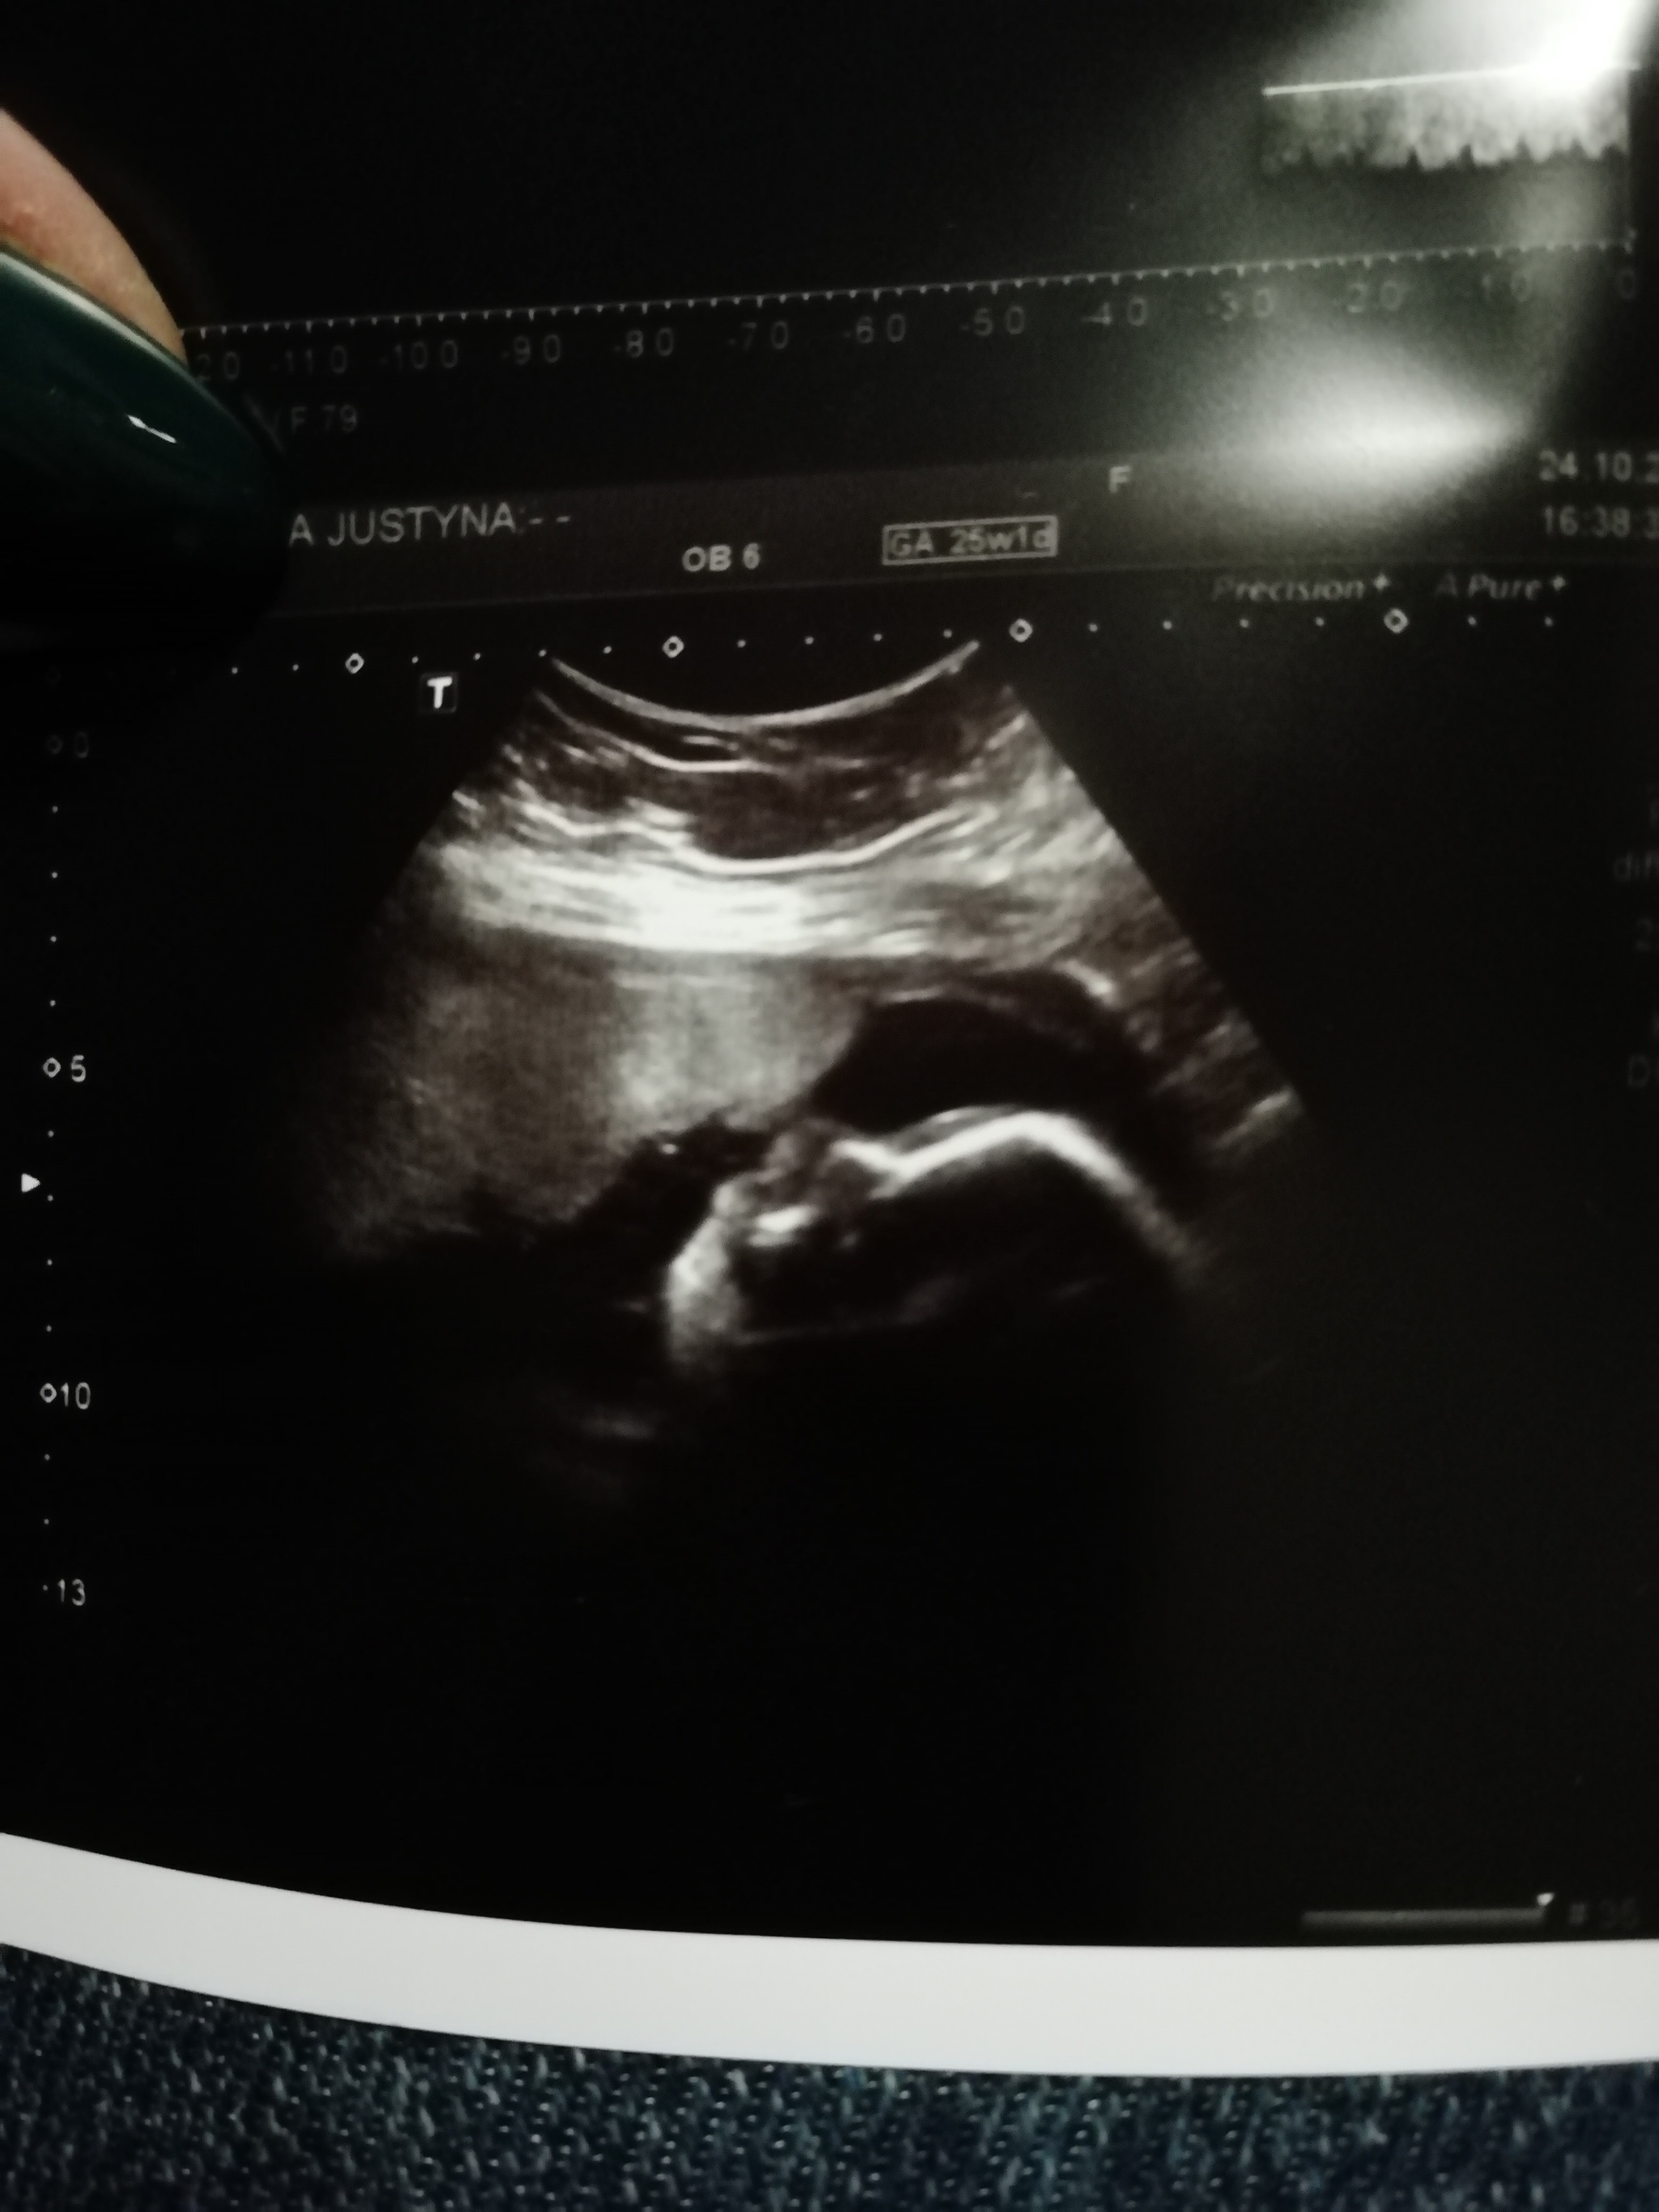

Tu podobno widac siusiaka, cos na ksztalt siusiaka, raczej siusiaka

IMG_20191024_205457.jpg